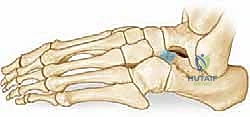

الالتصاق العظمي بين العقب والعظم الزورقي هو عيب خلقي يحدث أثناء التطور الجنيني في رحم الأم. لسبب غير معروف تماماً (يُعتقد أنه خلل جيني في انقسام الخلايا الميزنخيمية الجنينية)، تفشل العظام في الانفصال التام عن بعضها البعض، مما يؤدي إلى تكون "جسر" أو "وصلة" غير طبيعية تربط بين الجزء الأمامي العلوي من عظم العقب، والجانب الخارجي (الوحشي) من العظم الزورقي.

هذا الجسر الشاذ يعمل كقفل ميكانيكي يعطل حركة المفصل تحت الكاحل والمفاصل المجاورة. عندما تُقفل هذه المفاصل، تفقد القدم قدرتها على امتصاص الصدمات، وتصبح صلبة ومتيبسة، مما يؤدي إلى تسطيح قوس القدم (القدم المسطحة الصلبة).

* علامة أنف آكل النمل (Anteater Nose Sign): في الصورة المائلة، يظهر العظم العقب مستطيلاً وممتداً نحو العظم الزورقي بشكل يشبه أنف حيوان آكل النمل. هذه العلامة الإشعاعية كلاسيكية ومؤكدة للالتصاق بين العقب والزورقي.